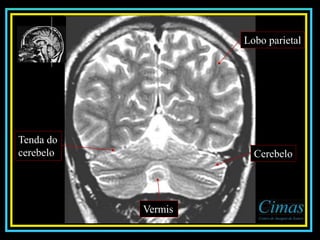

Lobo parietal

Cerebelo

Vermis

Tenda do